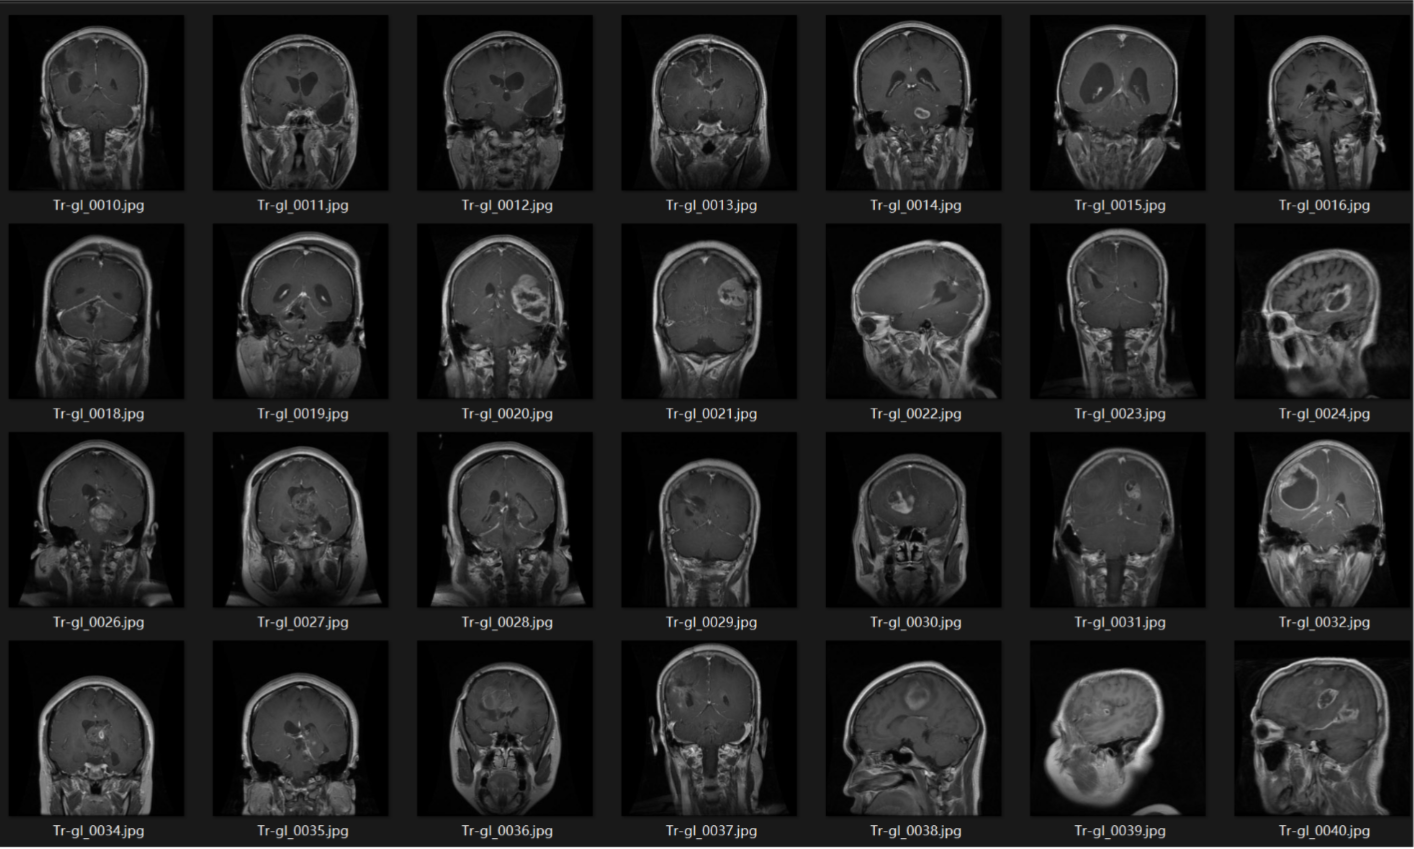

脑肿瘤MRI识别